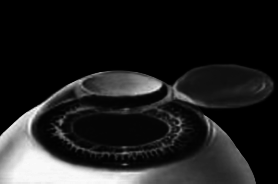

Стоит один раз моргнуть и лоскут скомкается и зрения не будет. Его бы пришить на место. Но швы деформируют роговицу. Все проще. Лоскут разглаживают мокрым тупфером, прижимая его ровненько к старому месту (рис. 7 и 8). Только место не старое, с роговичного ложа удалили несколько микрон в виде причудливой ямки (при коррекции близорукости).

Рис. 7. При коррекции близорукости на роговичном ложе формируется «ямка».

Иллюстрация с сайта Международного лазерного центра www.optics.ru

Рис. 8. Роговичный лоскут укладывается на место.